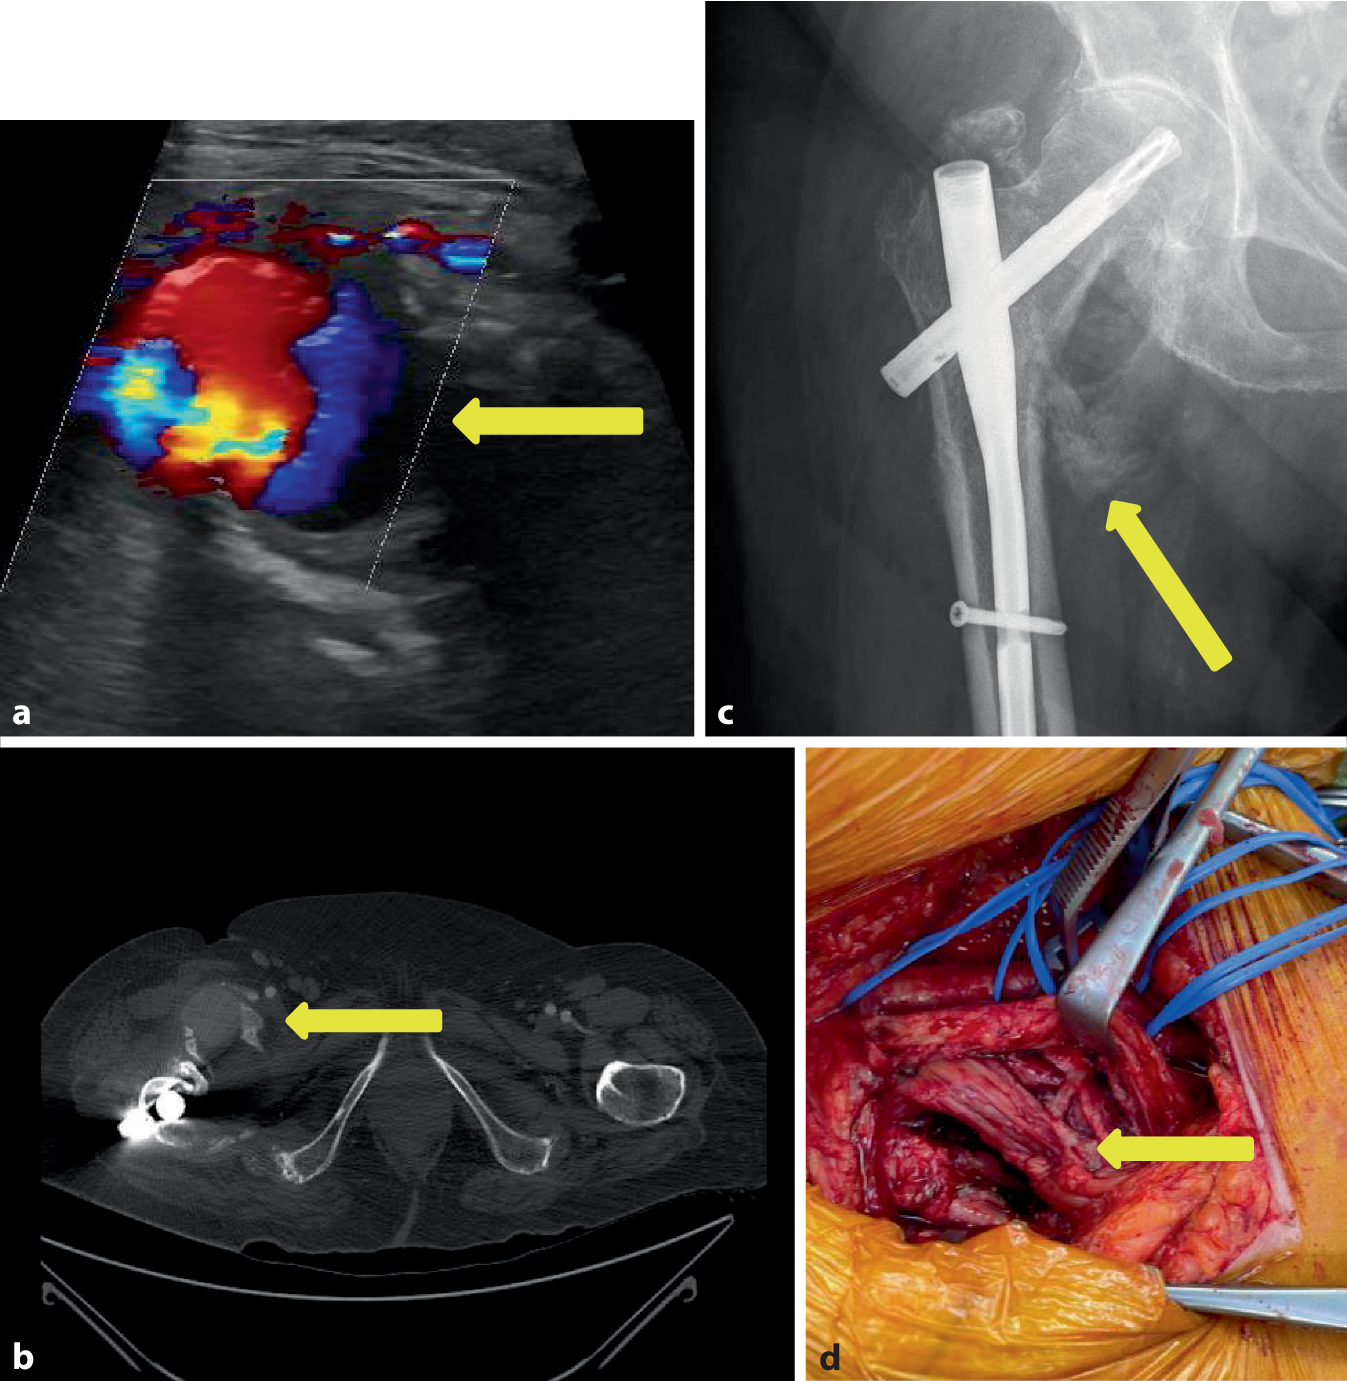

Im Rahmen eines Sturzes erlitt eine 92-jährige Patientin eine pertrochantäre Femurfraktur rechtsseitig, die durch eine geschlossene Reposition und Osteosynthese mittels proximalen Femurnagels Antirotation (PFNA)-Verriegelungsnagel (Fa. DePuy Synthes, Oberdorf, Schweiz) rechts versorgt wurde. Bei guter physischer und psychischer Compliance wurde die Patientin postoperativ frühzeitig mobilisiert und in die Häuslichkeit entlassen. Die Vorstellung in der Gefäßchirurgie erfolgte nach 2 Monaten aufgrund einer peripheren arteriellen Verschlusskrankheit (pAVK) Stadium IV mit Zehennekrosen rechts. Die Diagnostik mittels farbkodierter Duplexsonographie zeigte eine ca. faustgroße echoleere Raumforderung neben dem Schenkelhals mit einer pulssynchronen Verwirbelung im Sinne eines Pseudoaneurysmas (Abb. 2a). Die CTA ergab neben einer ausgeprägten Unterschenkel-pAVK rechts ein monströses Pseudoaneurysma der A. profunda femoris rechts mit ausgeprägter perifokaler Verkalkung (Abb. 2b). Bereits in einer Nativröntgenaufnahme ist medial des Schenkelhalses eine schalenförmige Verkalkungsstruktur zu sehen (Abb. 2c). Aufgrund der begleitenden kritischen Ischämie des rechten Unterschenkels erfolgte der kombinierte Eingriff der offenen Resektion des Pseudoaneurysmas und Ligatur des perforierten Profundaastes (Abb. 2d) sowie die begleitende Ballonangioplastie des Unterschenkels, worunter es zu einer Stabilisierung der pAVK Stadium IV rechtsseitig kam. Der genaue Mechanismus der Entwicklung des Pseudoaneurysmas verblieb letztlich nicht völlig geklärt, da der Operationsbericht keinen Hinweis auf einen untypischen Operationsverlauf ergab.

Abb. 2

Fall 2: Pseudoaneurysma der A. profunda femoris rechts. a Farbkodierte Duplexsonographie des Pseudoaneurysmas mit typischem Farbwechsel (gelber Pfeil), b CT-Angiographie mit Nachweis des Pseudoaneurysmas der rechten Inguinalregion (gelber Pfeil), c Nativröntgen der mit einem PFN-Nagel versorgten pertrochantären Fraktur mit zirkulärer Verkalkung (gelber Pfeil), d intraoperative Darstellung der Pseudoaneurysmahöhle und des verletzten Profundaastes (gelber Pfeil)